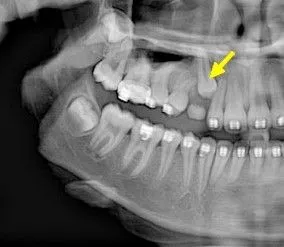

Surgical Exposure of Impacted Teeth

Sometimes, permanent teeth—especially upper canines—fail to erupt on their own. When this happens, your orthodontist may recommend a minor surgical procedure to uncover the tooth and guide it into place. At our practice, Dr. Sakhai works closely with your orthodontist to perform either an open exposure or expose and bond procedure, depending on your specific needs.

Open exposure is used when the impacted tooth is close enough to the surface that it can likely erupt on its own once uncovered. Dr. Sakhai gently removes the overlying gum tissue and sometimes a small amount of bone to expose the crown of the tooth. A periodontal dressing may be placed, and the area is left open to allow the tooth to naturally erupt into position over time with orthodontic guidance.

Expose and bond is typically done when the tooth is deeper or needs assistance to move into place. After exposing the tooth, Dr. Sakhai bonds a small orthodontic bracket and chain to it. The chain is later connected to your braces or aligner system so your orthodontist can gradually guide the tooth into its correct position over the course of treatment.